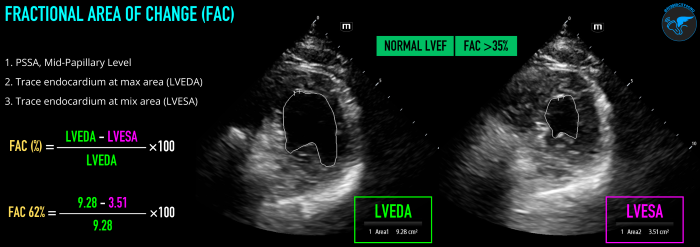

Fractional Area of Change (FAC)

FAC measures the change in left ventricular area between diastole and systole to estimate LVEF. The operator will first obtain a PSSA view at the mid-papillary level. Freeze the image on screen, and scroll through to find the maximum area (left ventricle end diastolic area, LVEDA) and the minimum area (left ventricle end systolic area, LVESA). At each of these points, trace around the endocardial border of the LV, ensuring not to include the myocardium or papillary muscles. FAC% = (LVEDA - LVESA)/LVEDA x 100 (Figure 4). Like FS, FAC measures a change in area/distance and does not result in a value that is the LVEF, which is a measure of volume. LVEF can be estimated based on the FAC% value.10 Regional wall motion abnormalities, preload, and afterload can significantly influence FAC.

LVSF_Figure 4_Fractional Area of Change v2.pngFigure 4. Fractional Area of Change (FAC) technique and normal values visual guide.